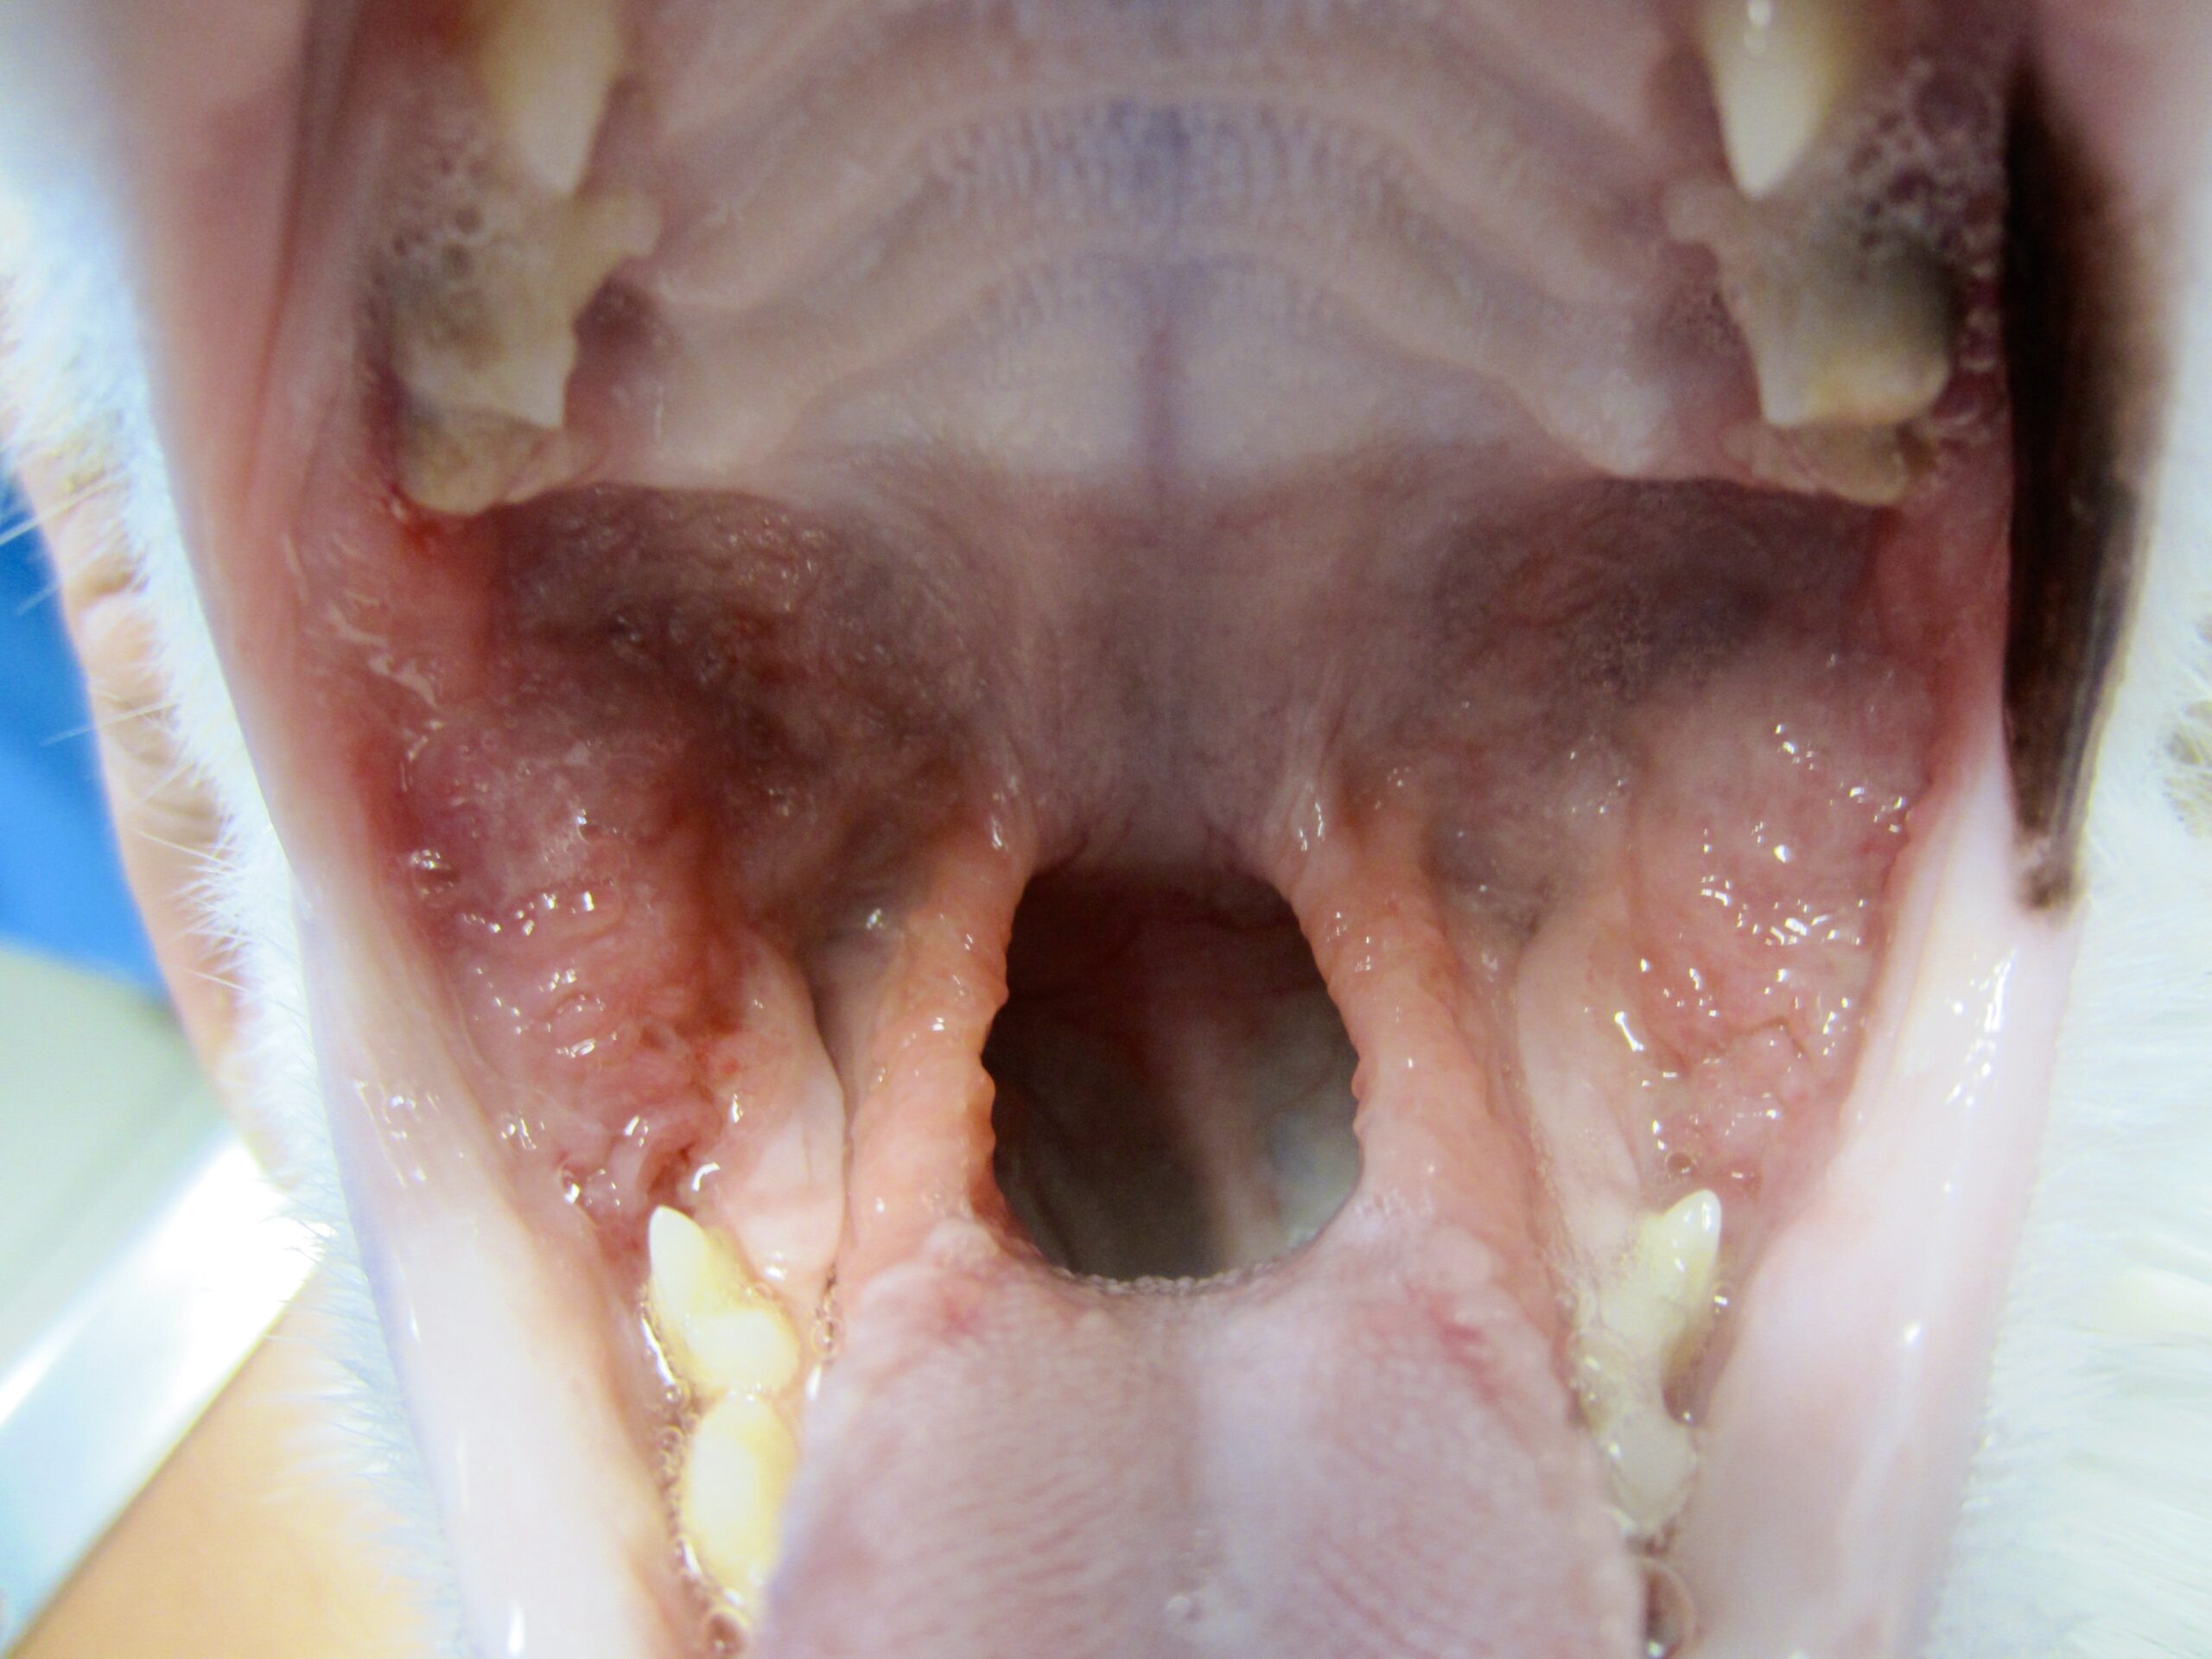

Bon, si on osait, on dirait que jusque-là, ça n’allait pas encore trop mal. (On a bien dit : si on osait). Les inflammations de la gencive et du parodonte sont bien embêtantes, mais restent à peu près localisées autour des dents atteintes ; si on ne traîne pas trop et qu’on met en place des soins dentaires et, si nécessaire, quelques extractions, on récupèrera le plus souvent une bouche saine. Le problème, c’est que le chat ne fait décidément rien comme tout le monde, et que l’inflammation peut, sous certaines conditions que nous détaillons juste après, gagner le fond de la bouche : c’est la stomatite caudale, encore appelée palatoglossite. (Glossite, c’est quand la langue est enflammée, et palato, c’est pour le palais). Et là, ça se traite beaucoup moins bien. Les photos ci-dessous montrent à quoi ça ressemble : on imagine ce que peut endurer le pauvre chat !

Bon alors là, c’est l’horreur complète, Hiroshima après la bombe. Pour ceux qui auraient du mal à s’y reconnaître, tellement c’est modifié, on a le chat en face de nous, bouche ouverte. En haut, c’est le palais, en bas, c’est la langue, de chaque côté on a les dents, et la cavité au milieu, c’est le passage pour les aliments. L’atteinte est symétrique, elle concerne tout le fond de la bouche (= stomatite caudale), en particulier l’arrière du palais, les piliers de la langue (ou piliers du pharynx), et la langue elle-même (= palatoglossite) et peut s’étendre à l’intérieur des joues. La photo de gauche a été prise chez un chat de sept ans, juste avant les extractions dentaires (on en parle plus loin, avec le traitement). À droite, la même en pire, chez une chatte Maine Coon de un an.